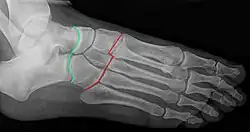

Früh gealtert und kränklich verfasste Chopart eine große Abhandlung über Krankheiten der Harnwege und beschrieb eine von ihm 1791 durchgeführte und nach ihm benannte Methode der teilweisen Fußamputation mit Exartikulation im Fußwurzelgelenk, die zuvor von Huguet von Abbeville 1746 als Möglichkeit nachgewiesen wurde, von Lorenz Heister angedeutet und 1780 von Johann Nepomuk Hunczovsky erstmals bei du Vivier in Rochefort an einem achtjährigen Jungen ausgeführt wurde. Sein treuester Freund war sein Lehrer Desault, ebenfalls Mitglied der Académie royale de chirurgie in Paris, der kurz vor ihm starb. Die Behandlung des kranken Desault erfolgte durch Chopart und Corvisart.[3]

Nach ihm ist die Chopart-Linie (Articulatio tarsi transversa) am Fuß-Skelett benannt, entlang der eine Fußamputation möglich ist.